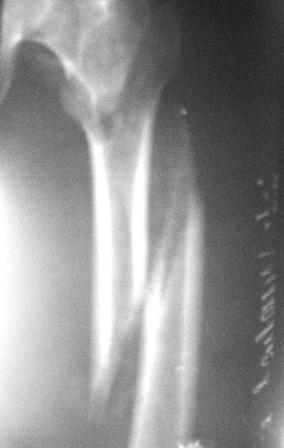

Больному 50л. В отдаленном от центра р-не ДТП 6.12.08г. д-з " тяжелая ЧМТ, мн.перломы ребер слева,отрыв ножки селезенки, повреждение п/ж железы, з/двойной перелом прав.бедра.

После экстрен. хирургических вмешательств, конечность фиксирована кокситной гипсовой лонгетной повязкой. Кома 2 нед, нагноение п/о раны живота, посттравмат. пневмония. 20.01.09г. переведен к нам. Постельный больной, ослабленный,бледный, весом 56кг: свищ п/о раны перед. брюшной стенки с сукровичным выделением, гипс снят - деформация и укорочение бедра на 6 см, в обл перелома есть спайка. слабо, но активно поднимает ногу, контрактура т/б и коленных суставов. Обшеукреп. лечение, компоненты крови, общ. массаж, ЛФК и больной активизирован, начал ходить с костылями, движения в суставах почти восстановлены. НВ-112, эр-3,5млн. Наш план блокир. и/м остеосинтез. Имеется гвозди для ВНПБ ЦИТО, но PFN не имеется

Лучше сделать остеоклазию на уровне диафиза секциями аппарата (ротацией), затем проводить дистракцию темпом 2-4 мм/сут дробно, в пределах переносимости пациентом. После восстановления длины и сопоставления диафиза по оси закрыто заштифтовать. Имеющийся стержень вполне подойдет, поскольку вертельный перелом уже не будет требовать остеосинтеза.